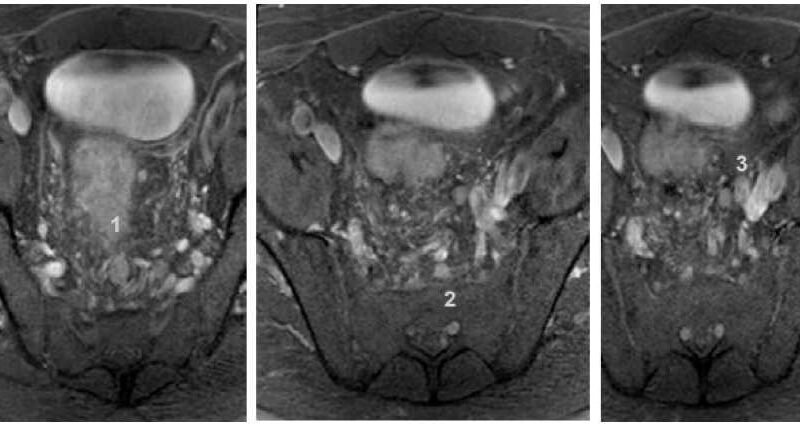

Lectura: 25 minutos / Autora: Diana Marcela Bolaños Ordoñez Tutor: Dr. Gustavo San Martín Resumen Los tumores neuroendocrinos del páncreas, específicamente los insulinomas, son neoplasias raras, pero potencialmente letales, que requieren un diagnóstico y tratamiento precisos. Se han reportado en una a cuatro personas por millón cada año, siendo más frecuente en varones que en mujeres, y pueden ocurrir a cualquier edad. La detección temprana y la localización exacta de estos tumores son fundamentales para la planificación del tratamiento quirúrgico y el seguimiento posoperatorio. La presentación del insulinoma es habitualmente benigna, con una masa menor a 2 cm de diámetro. Otra forma de presentación consiste en la presencia de múltiples insulinomas (10 % de los casos). En este trabajo se abordan cuatro casos clínicos de insulinoma. Palabras clave: insulinoma, páncreas, tumores neuroendocrinos, diagnóstico, planificación, tratamiento quirúrgico. Introducción Los tumores neuroendocrinos del páncreas, específicamente los insulinomas, son neoplasias raras, pero potencialmente letales, que requieren un diagnóstico y tratamiento precisos. Se han reportado uno a cuatro casos por millón cada año, siendo más frecuente en varones que en mujeres. Pueden presentarse a cualquier edad.(1) La detección temprana y la localización exacta de estos tumores son fundamentales para la planificación del tratamiento quirúrgico